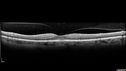

70 year old female diagnosed with diabetes 2 years ago. Her blood pressure was normal at 116/73. She has vision loss for 6 months in both eyes. VA is 20/100 OU. OCT-A shows macular ischemia.

Diabetic Macular Ischemia - Enlarged FAZ - OCT-A477 views70 year old female diagnosed with diabetes 2 years ago. Her blood pressure was normal at 116/73. She has vision loss for 6 months in both eyes. VA is 20/100 OU. OCT-A shows macular ischemia.00000